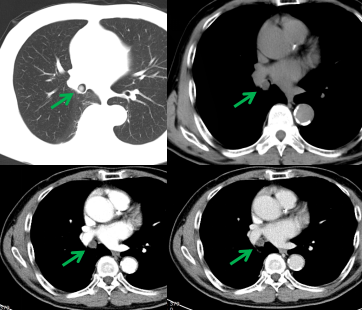

老年男性,體檢胸部CT檢查發(fā)現(xiàn)右肺中間段支氣管及右肺中葉支氣管不通暢,右肺中葉肺不張,右肺下葉炎癥。患者無咳嗽、咳痰、胸悶、氣短、咯血等不適,飲食、睡眠可,大小便無異常,近期體重無明顯下降。既往有“高血壓”“心臟早搏”病史,吸煙30余年,每日1包,無飲酒嗜好。腫瘤標志物無明顯異常。完善胸部強化CT檢查提示支氣管腔內腫瘤,建議支氣管鏡檢查(圖1)。

圖1,右肺中間段支氣管結節(jié)(綠箭),增強掃描輕度強化。